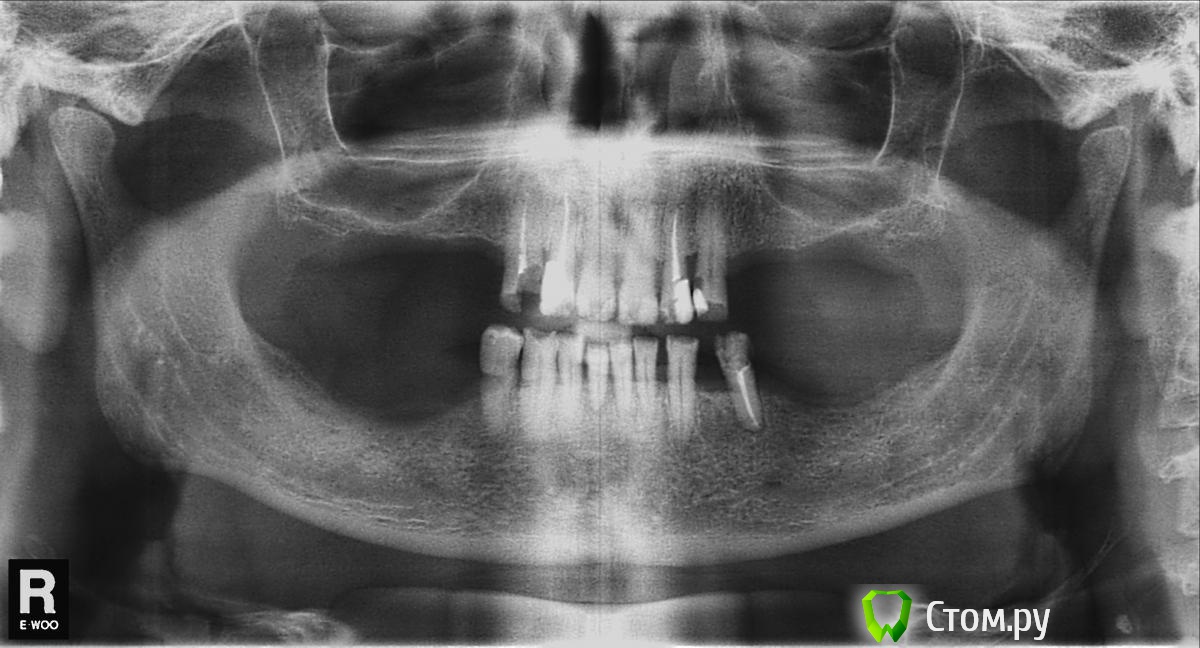

santos29 Опубликовано 27 ноября, 2013 Поделиться Опубликовано 27 ноября, 2013 Друзья, помогите пожалуйста советом. Начитался разных форумов и прочей инфы, был на 4 консультациях и в результате решил: сохранить все оставшиеся зубы, залечив их, зашинировать верх и низ, а затем установить нейлоновые зубные протезы. Мое решение основано на том, что с залеченными не обточенными своими оставшимися зубами в дальнейшем я еще возможно смогу выбирать варианты учитывая совершенствование стоматологии. Кроме того "голливудская" улыбка мне не к чему, главное что бы можно было нормально кушать. Будет ли работать такая конструкция хотя бы в течении 3 лет? Нейлоновые протезы видимо тоже бывают разные, поэтому хотелось бы что нибудь современное, получше, полируемые и т.д. Ссылка на комментарий

santos29 Опубликовано 28 ноября, 2013 Автор Поделиться Опубликовано 28 ноября, 2013 Имплантацию не рассматриваете? Импланты в таком объеме мне не по зубам, но думаю, что возможно четвертый левый нижний имплант придется поставить (если конечно пятый удастся сохранить - говорят, что он проблемный) Ссылка на комментарий

santos29 Опубликовано 29 ноября, 2013 Автор Поделиться Опубликовано 29 ноября, 2013 Вчера был у доктора, составили план: депульпация (кроме 2 верхних центральных), снизу 3 удалять (два центральных и левый пятый), металокерамика на опорные и протезы Quattro Ti «Dental-D». Какое отношение у профи к таким протезам? Ссылка на комментарий

santos29 Опубликовано 29 ноября, 2013 Автор Поделиться Опубликовано 29 ноября, 2013 Шинировать низ сказали бесполезно, потому что под центральными подвижными со временем может воспалиться десна и тогда потеряю все! Ссылка на комментарий